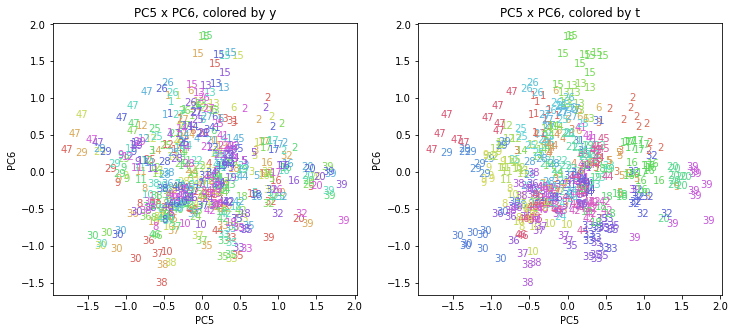

PCAの結果の第n主成分をPCnと表記します。

医療費データの場合と同様に、PCAの結果を見やすく表示するため、seabornのカラーパレットを使って、年月別、都道府県別に色分けして図示してみます(左側が年月別に色分け、右側が都道府県別に色分け)。PC1~PC8まで表示しました。

都道府県番号の表示

上の色分けだけでは都道府県が区別しにくいので、医療費データの場合と同様に、点の代わりに都道府県番号をプロットした図も描いておきます(色分けは上と同じ)。

医療費データの場合ほどはっきりとはしていませんが、PC2が概ね時間の経過を表す成分で、残りの成分が時点によって変わらない地域の特徴を表す成分となっているようです。

また、PC1×PC3を見ると、47沖縄が他の都道府県からかなり離れたところに位置しており、沖縄の地域差が際立っているのが分かります。これは、以前別の記事で年齢階級のない健診データでPCAを実行した場合と似た結果となっています。